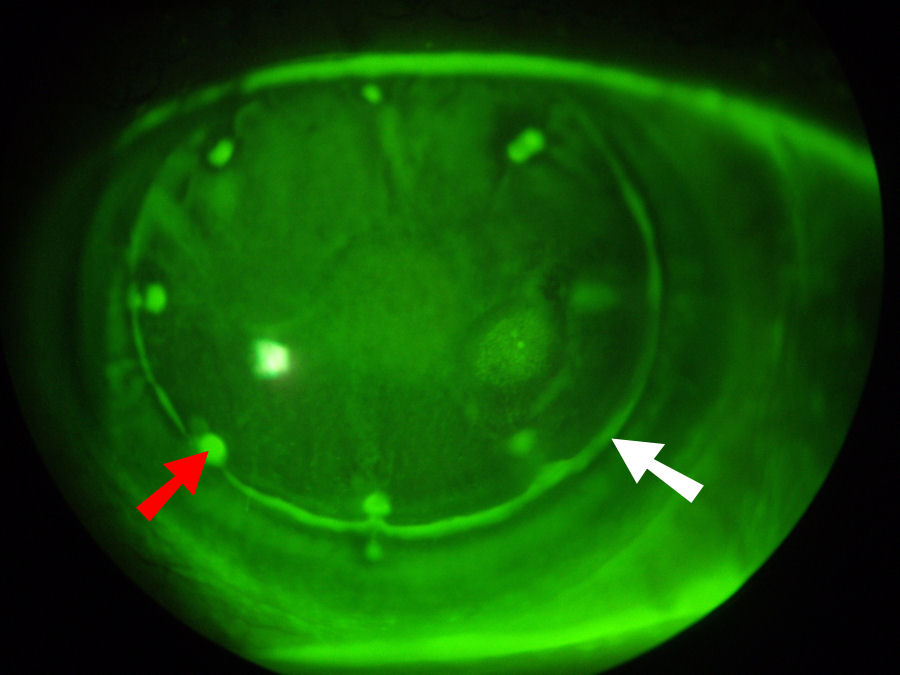

Глаз, изображенный на фотографии ниже, был подвергнут кондуктивной кератопластике (КК) в попытке исправить зрение пациента после сверхкоррекции LASIK. До этих операций у пациента было отличное зрение в очках. Сейчас у пациента крайне нечеткое и искаженное зрение, которое невозможно исправить с помощью очков. Нажмите на фотографию, чтобы увеличить.

КК был введен для лечения дальнозоркости. КК использует иглоподобный зонд для доставки радиочастотной энергии (тепла) к коллагену периферической части роговицы в кольце индивидуально расположенных точек. Нагревание приводит к сокращению коллагена роговицы, что приводит к утолщению центральной части роговицы. Ниже вы можете четко видеть восемь точек, расположенных кольцом вокруг роговицы, в которые были введены зонды для КФК. Красная стрелка указывает на одно из мест КФК. Сразу за кольцом СК-пятен находится край лоскута LASIK, обозначенный белой стрелкой. Такие повреждения роговицы никогда полностью не заживают.